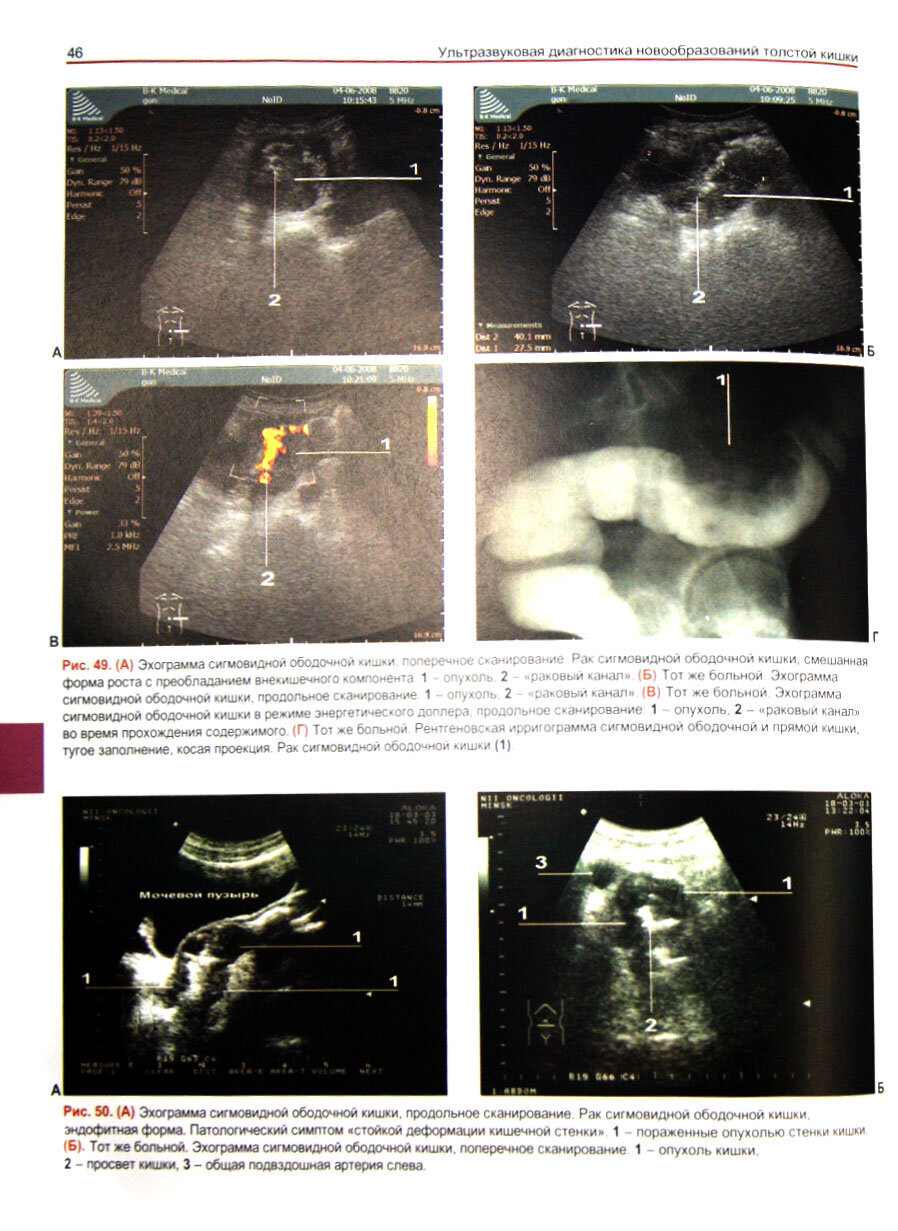

Ультразвуковая диагностика новообразований толстой кишки (Кушнеров Александр Иванович); Медицинская литература, 2014

В книге рассматривается оптимальное применение УЗИ в комплексе с другими методами лучевой диагностики для выявления новообразований толстой кишки. Особый упор делается на диагностике ранних стадий колоректального рака.

Описаны методико-семиотические, методологические и технические аспекты ультразвукового исследования кишечника, позволяющие оценить состояние мягких тканей при их послойной визуализации, определить степень инвазии опухоли в клетчатку и окружающие органы, наличие метастазов в регионарных и отдаленных лимфатических узлах, а также во внутренних органах. Диагностике осложненных форм и метастазов рака толстой кишки посвящены отдельные главы.

Особое внимание уделено ультразвуковому исследованию после оперативного и лучевого лечения опухолевых заболеваний толстой кишки.

Для специалистов по ультразвуковой и лучевой диагностике, онкологов, гастроэнтерологов, студентов медицинских вузов.